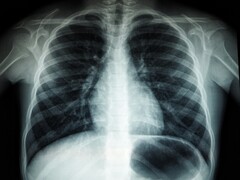

The researchers report that just one hairstyling session lasting 10–20 minutes can result in the inhalation of more than 10 billion nanoparticles. They say this level of pollution is comparable to what you will get in the middle of a dense highway traffic. Given the size of these particles, they can easily penetrate deep into the lungs. This may lead to health issues like respiratory stress, lung inflammation, and cognitive decline.